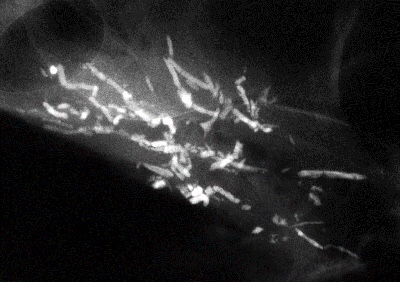

👉The most frequent malignant, ductal “casting type” calcifications are fragmented, linear, and branching, and they are the most reliable mammographic sign of malignancy.

👉The presence of fragmented and/or dotted casting type calcifications on the mammogram restricted to one lobe is a pathognomonic sign of a diffuse, grade 3 breast cancer subtype that originates in the major ducts and usually has a solid or micropapillary pattern.

👉Traditionally, this subtype has been called “comedo carcinoma.”

👉The cancer cells either produce a viscous, proteinaceous fluid which gradually concentrates and eventually calcifies, or they undergo necrosis (apoptosis) followed by calcification.

👉In both instances the intraluminal pressure increases, distending the ducts considerably.

👉Dotted casting type calcifications have been referred to as “snake skin-like calcifications” and they accumulate in the fluid produced by either micropapillary or solid cancer cell growth patterns.

👉The tips of the micropapillary growths may become detached and eventually calcify, contributing to the intraluminal calcifications.